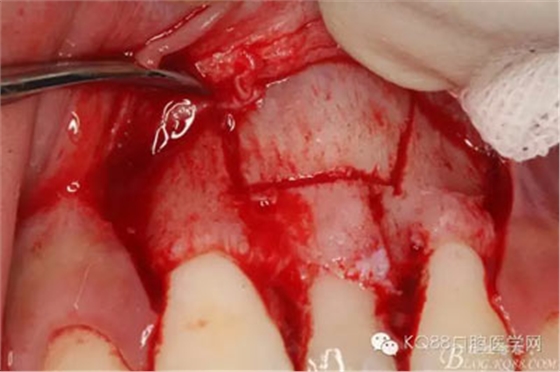

圖7.翻瓣、注意是全厚瓣。

圖8.翻開牙齦粘膜瓣,可見左乳Ⅰ根方骨面隆起

圖9.超聲骨刀去除隆起的骨壁

圖10.形成梯形骨縫